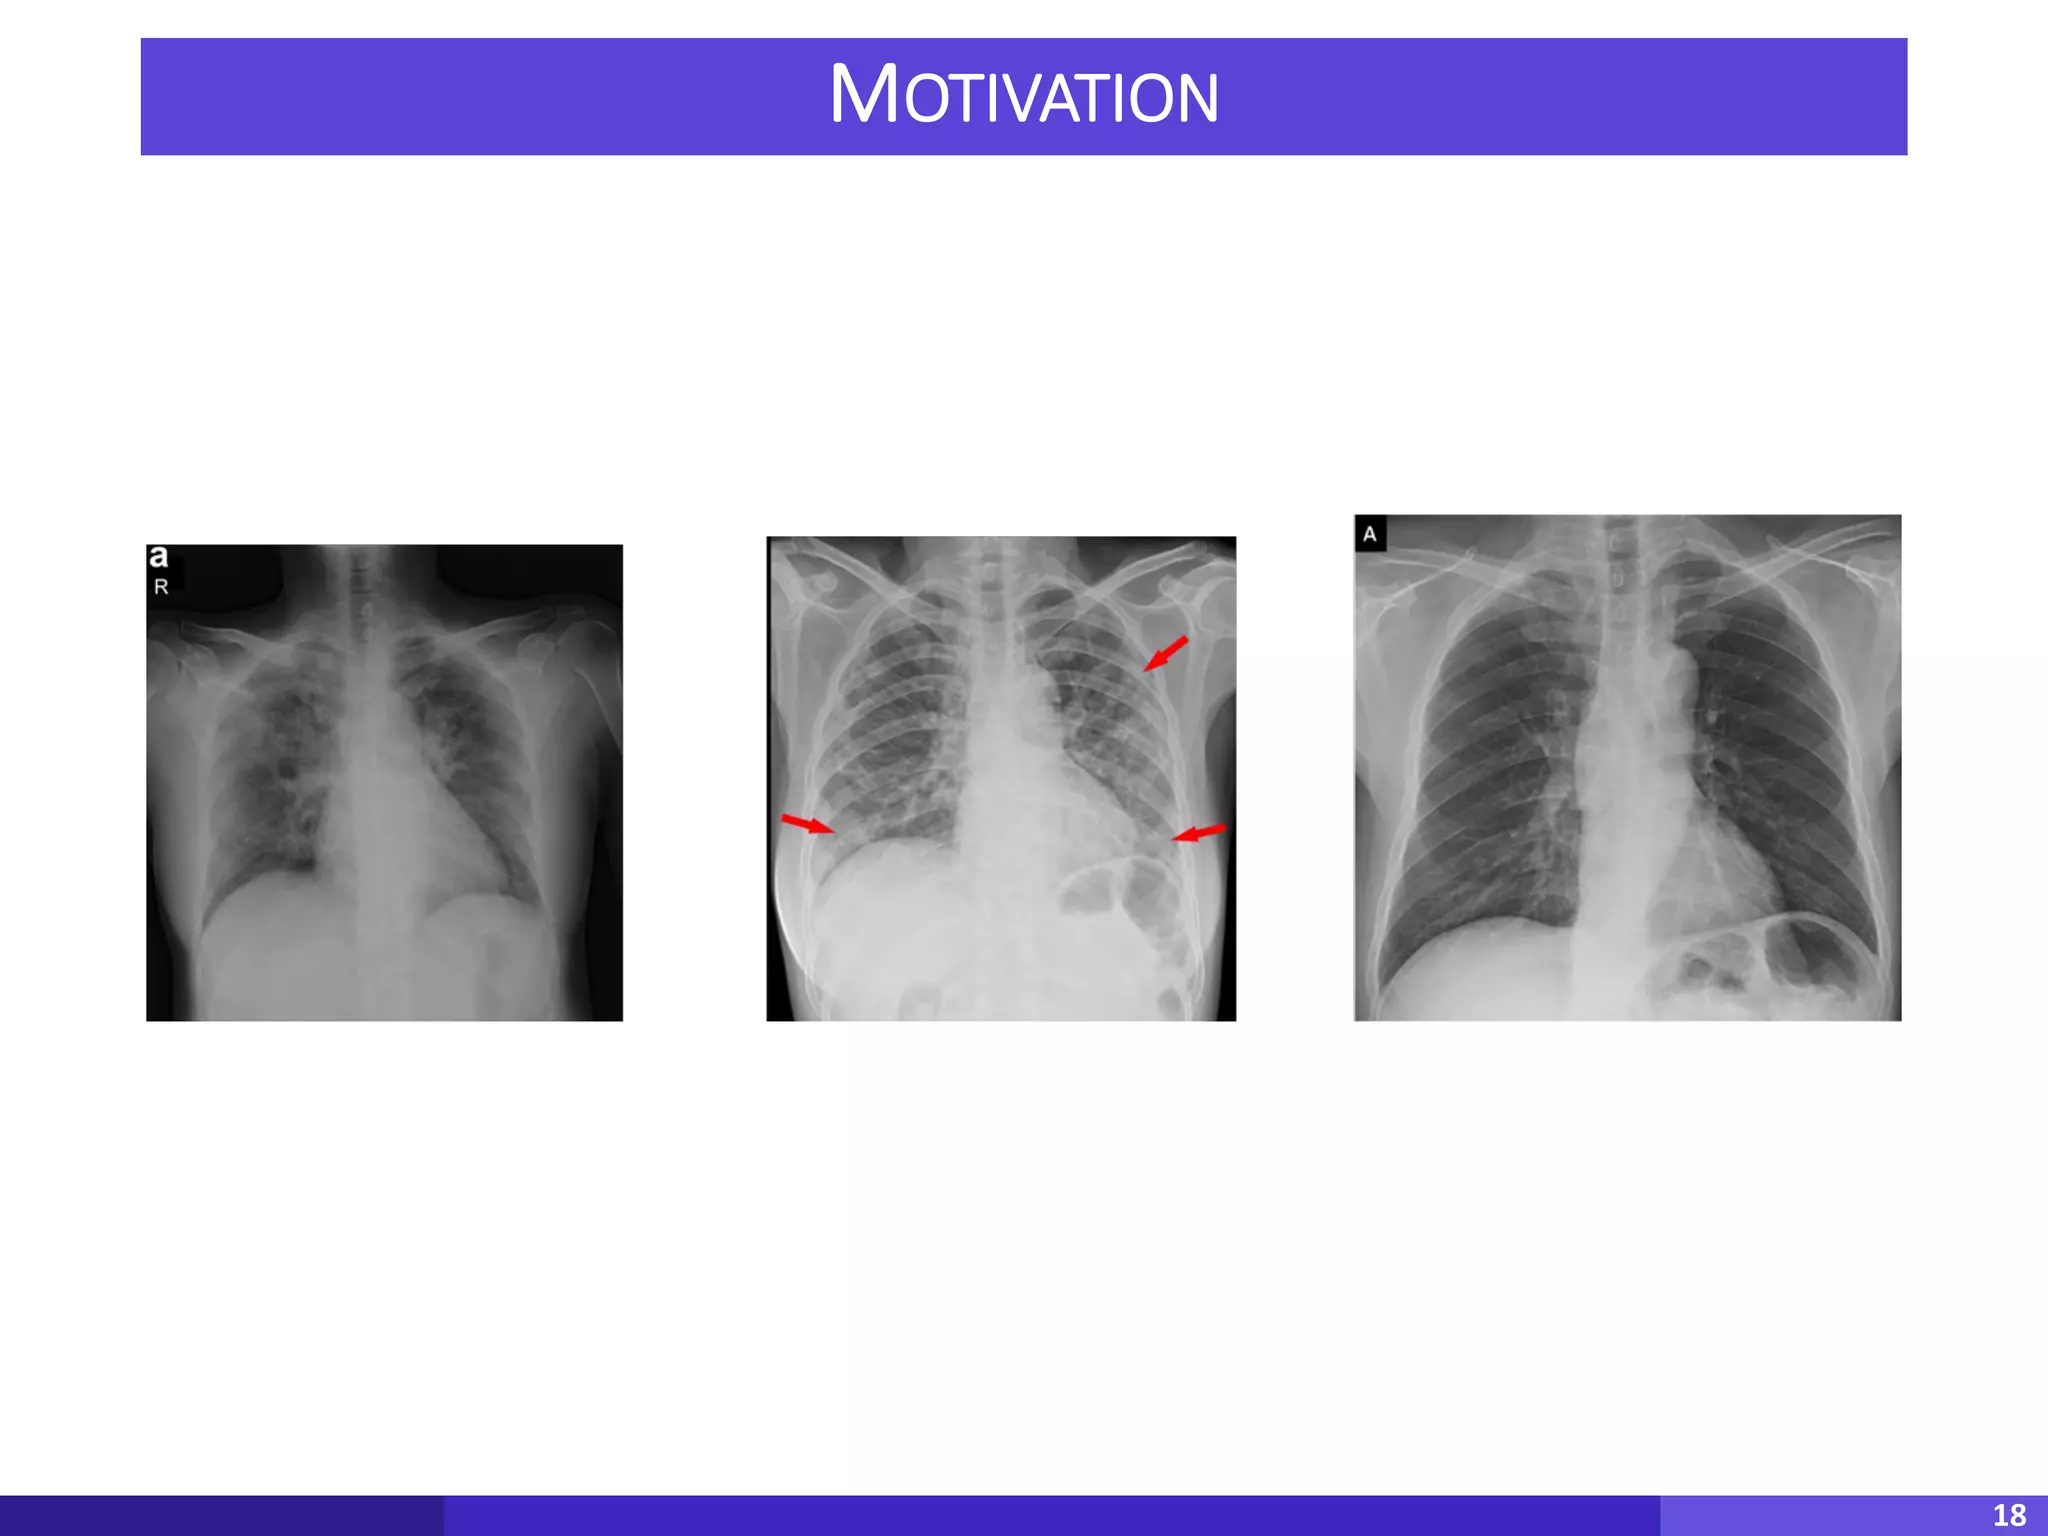

• Corona virus is one of the most deadly virus with

highest number of causalities across the world

• We don’t have the enough mechanism to detect

the Corona from the X-Ray images

• Idea: Can we build ML models to detect positive

cases using X-ray images?

MOTIVATION

18